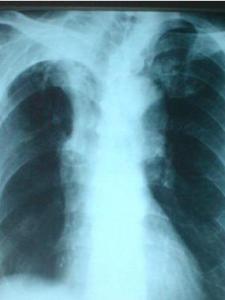

疾病检查

陈旧性肺结核陈旧性肺结核胸片。

诊断鉴别

陈旧性肺结核陈旧性肺结核根据胸片可确诊。